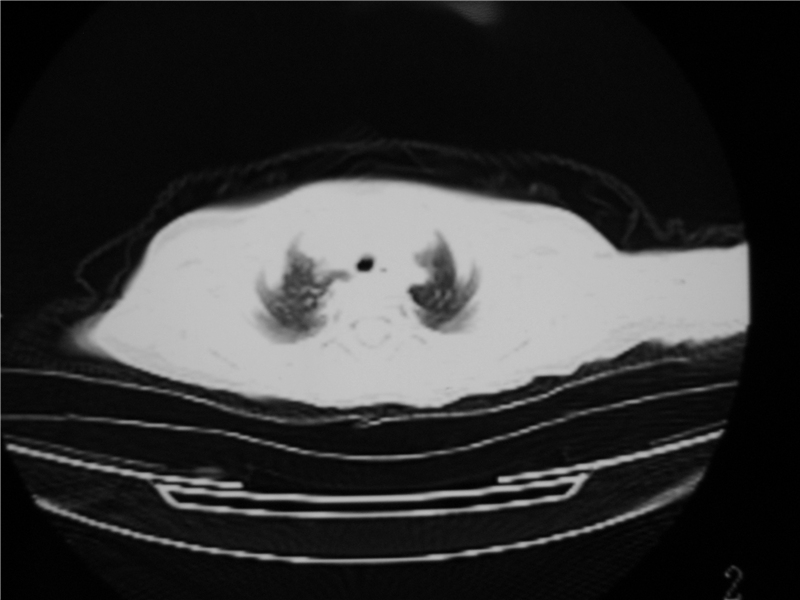

标题: PED3236:男2岁进食花生米后发烧10天。

摄吸气及呼气相对比片,本例为有肺中叶阻塞性炎症、不张,右肺下叶阻塞性炎症。

1)右肺炎症并右肺中叶肺不张,右肺上叶充气不良。2)右侧支气管异物不排除。

楼上师兄说拍呼气吸气相。但工作中很难做到-2岁小孩不会配合。我们这里真没成功过。多是在透视下看看

再有,我们16排ct有气管重建功能,肯异物效果可以。